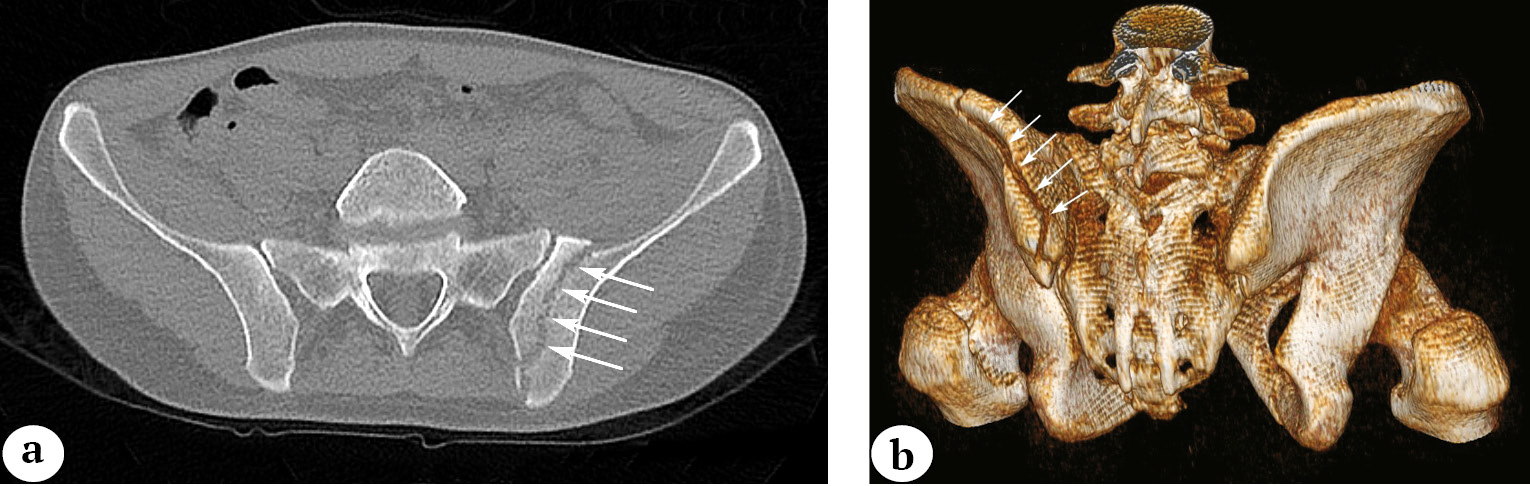

Through clinical observations and stress tests under anesthesia, we determined that vertical fractures are unstable and require surgical treatment, unlike horizontal fractures, which are relatively unstable. Vertical fractures can further be categorized into transverse and oblique. Transverse vertical fractures of the pubic bone’s base have their fracture plane predominantly oriented in the sagittal plane (Fig. 3).

Fig. 3. Vertical transverse fracture of the base of the pubic bone (the arrows indicate the fracture lines): a — 3D-CT image reconstruction; b — pelvic X-ray in the AP view

Another type of unstable vertical fracture of the base is the oblique fracture. In this case, the fracture line runs along the base of the pubic bone without affecting the symphysis, forming a distinctive sharp end of the fragment (Fig. 4). We propose to refer to such fractures as «longitudinal fractures of the pubic bone’s base.»

Fig. 4. Longitudinal fracture of the base of the pubic bone with a sharp ending: a — 3D-CT image reconstruction, the arrow indicates the sharp end of bone fragment; b — 2D-CT image reconstruction in the axial view, the arrows indicate the direction of the fracture along the base of the pubic bone

Such fractures can potentially be dangerous because the fragments may damage both the bladder and the venous plexus in the prevesical space when the pelvic ring is laterally compressed.